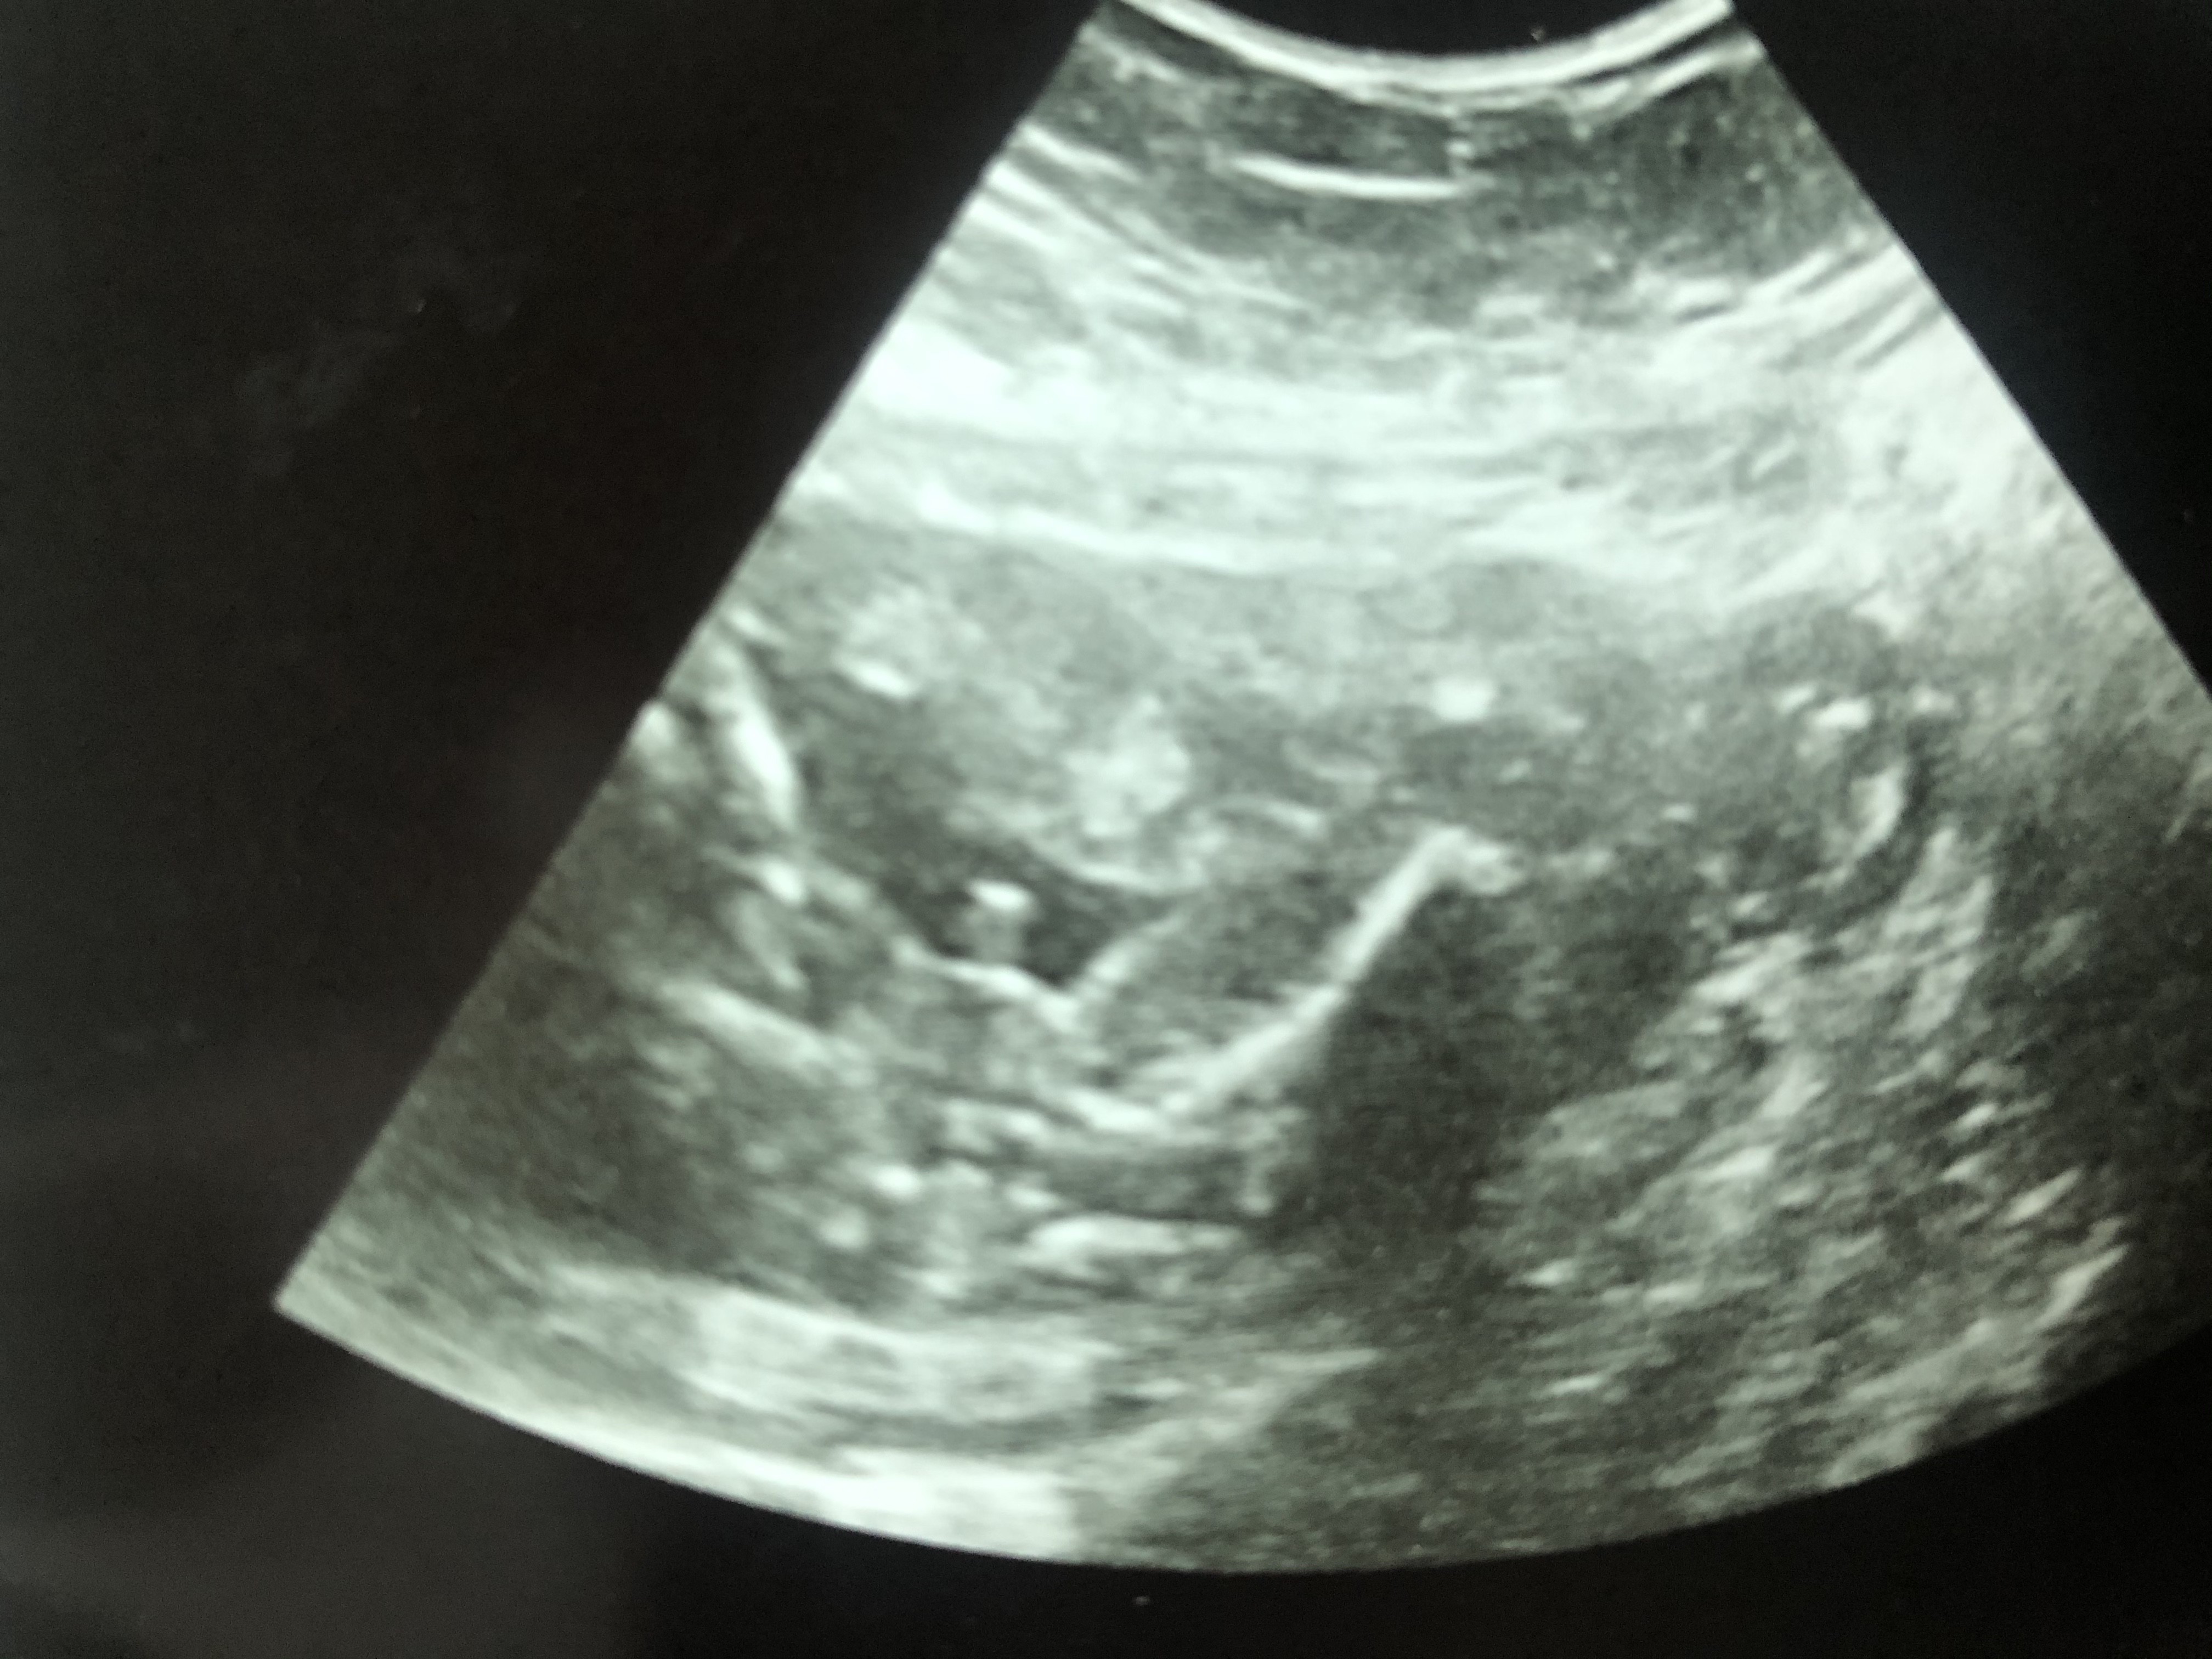

Pani Doktor mówi ze 100% chłopak ale jestem ostrożna. Mam już córkę no i wiadomo nie wiem jak wyglada siusiak na usgJakby coś tam było co by wskazywało że chłopiec

He he widać ptasioraCześć kochane, tez widzicie tu 100% chłopaka ? mamy termin na 15 marca

Kochana widać ptaka gołym okiem na 1000% synek będziePani Doktor mówi ze 100% chłopak ale jestem ostrożna. Mam już córkę no i wiadomo nie wiem jak wyglada siusiak na usgu mnie w całej rodzinie brak chłopców wiec szczęście ogromne, moja córka i mąż tez zadowoleni ale boje się, ze może jednak to nie siusiorek wiadomo lekarze czasem tez się mylą. Może któraś z Was ma synka i wyglądało to u niej podobnie

tak ogólnie jakby ktoś nie mógł się połapać w zdjęciu to są tam nóżki, dupka i ponoć siusiak